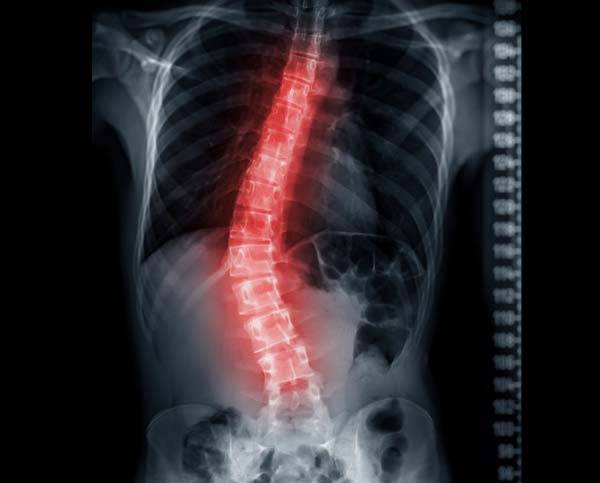

◇엑스레이∙신체검사로 진단… 필요하면 MRI∙CT도

척추측만증 진단에서 가장 중요한 것은 엑스레이 사진이다. 척추 전체를 촬영해 측만 위치와 몸의 균형을 확인할 수 있으며, 하지도 함께 촬영해 다리 길이의 차이에서 오는 영향을 판단한다. 신체검사로도 측만증 유무를 감별할 수 있다. 다른 원인이나 관련 증상을 감별하기 위해 어깨 높이와 견갑골 위치, 관절운동 이상 여부를 검사하기도 한다.

일반적인 측만증에는 엑스레이 외에 특별한 검사가 필요하지 않다. 그러나 어린 나이에 매우 심한 측만증을 갖고 있거나 급격한 측만 증가, 신경증상 등으로 다른 동반 질환이 의심될 때는 MRI(자기공명영상) 검사로 다른 이상이 있는지 확인한다. 또 통증이나 힘이 잘 들어가지 않는 등의 신경증상을 동반하면 추간판 탈출증 같은 통증 원인을 파악하기 위한 신체검사를 시행한다. 신경섬유종증과 연관있는 측만증으로 의심되면 피부 병변 확인이 필요하다. CT(컴퓨터단층촬영) 검사는 뼈의 기형을 판단할 수 있어서 수술치료, 특히 선천성 측만증 수술 시에는 필수다.